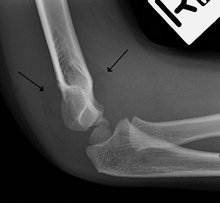

Fat pad sign

On an elbow X-ray, the fat pad sign, also known as the sail sign, suggests an occult fracture. Its name derives from the fact that it has the shape of a spinnaker (sail).[1] It is caused by displacement of the fat pad around the elbow joint. Both anterior and posterior fat pad signs exist, and both can be found on the same X-ray.

In children, a posterior fat pad sign suggests a condylar fracture of the humerus. In adults it suggests a radial head fracture. The fat pad sign only occurs after an intra-articular fracture.

The fat pad sign is invaluable in assessing for the presence of an intra-articular fracture of the elbow. An anterior fat pad is often normal. However a posterior fat pad seen on a lateral x-ray of the elbow is always abnormal. The patient will be unable to flex their elbow and requires orthopaedic input.[2]